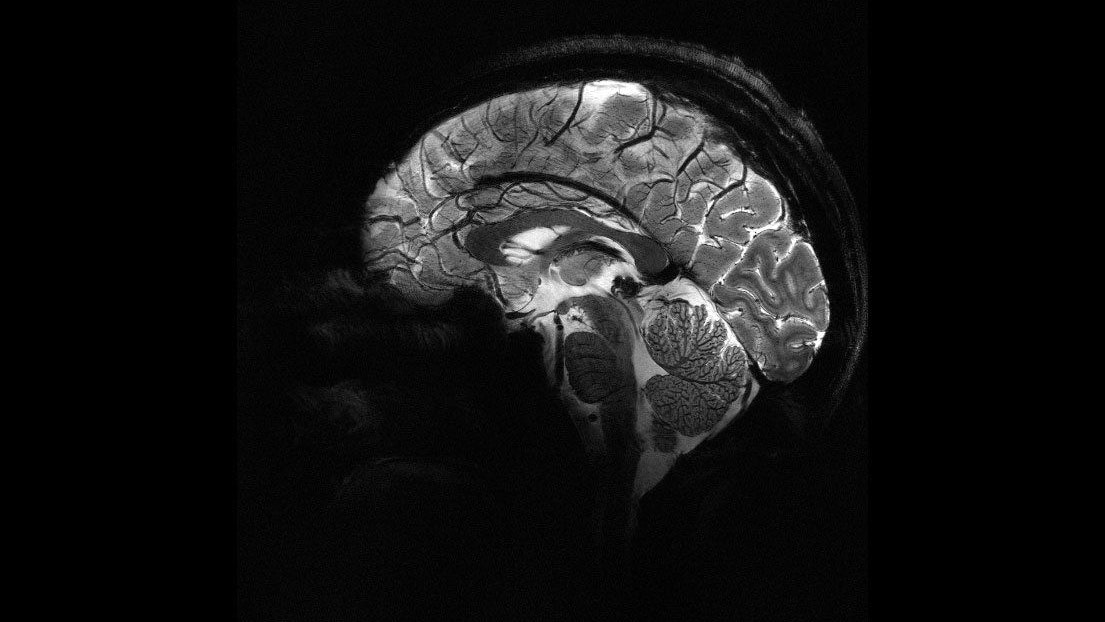

Das Gehirn in Darstellung des neuen Iseult-MRT.